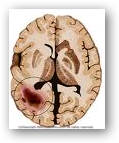

New research at Wake Forest University Baptist Medical Center suggests that a three-drug cocktail may

one day improve outcomes in patients with glioblastoma multiforme (GBM), a type of brain tumor with a dismal prognosis. Two of the drug candidates have been developed, and the team is working on the third all targeted to kill or impair cancer cells and spare healthy brain.